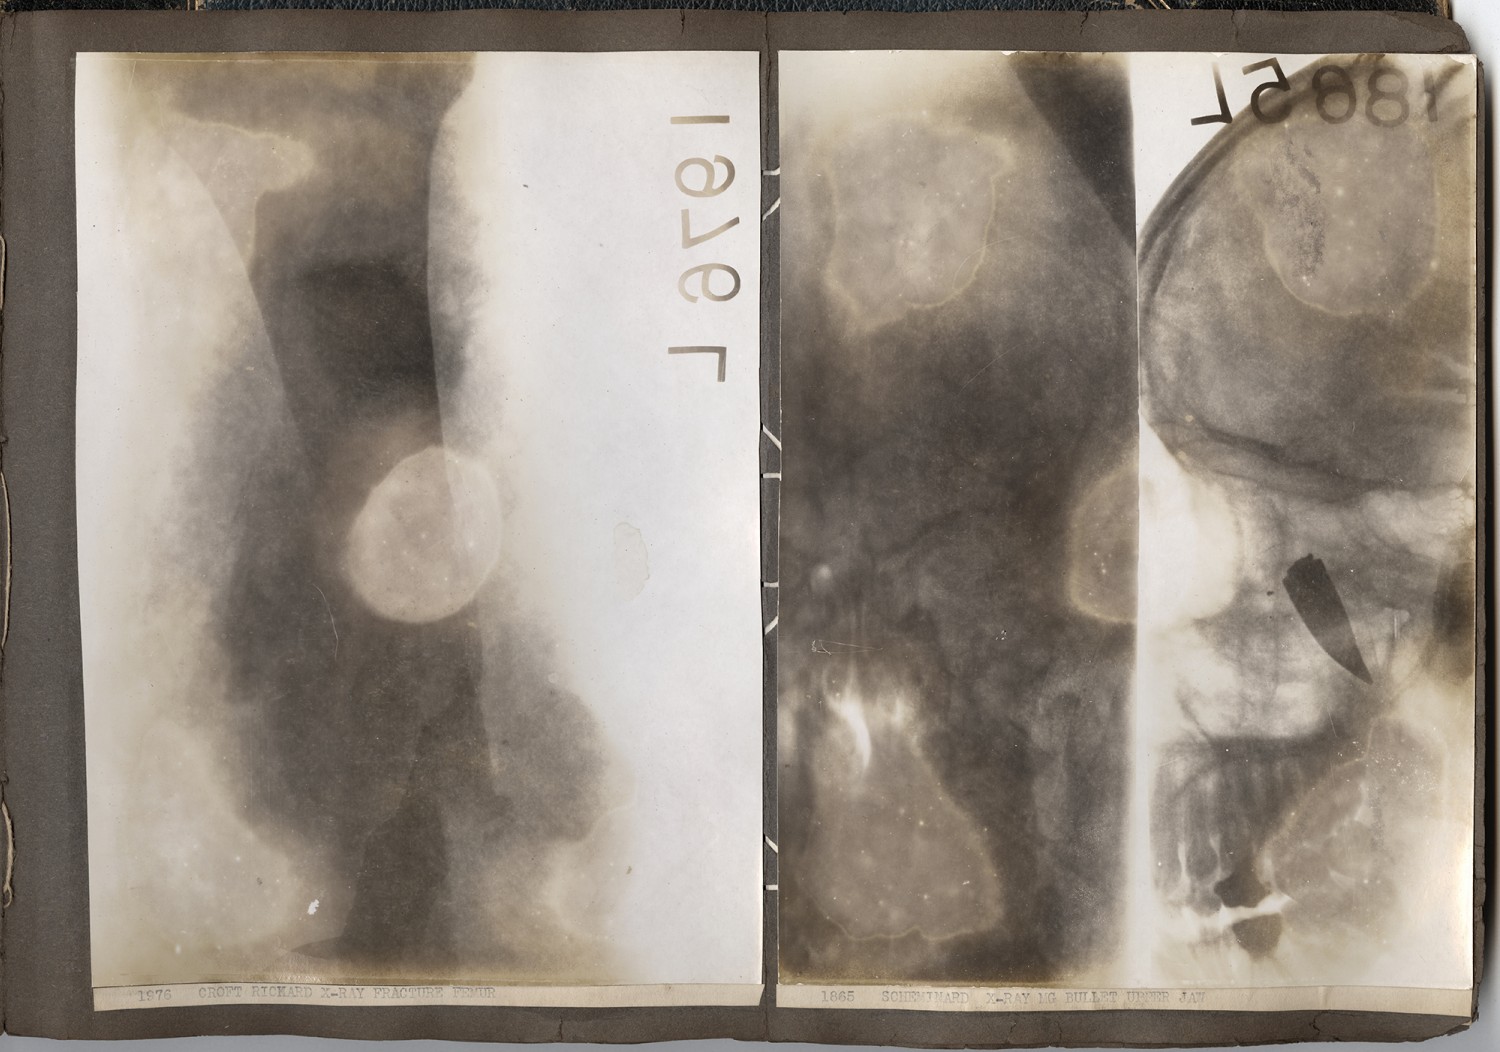

[x-ray, left] 1976 CROFT RICHARD X-RAY, FRACTURE FEMUR [x-ray, right] 1865 SCHEMINARD X-RAY, MG BULLET UPPER JAW